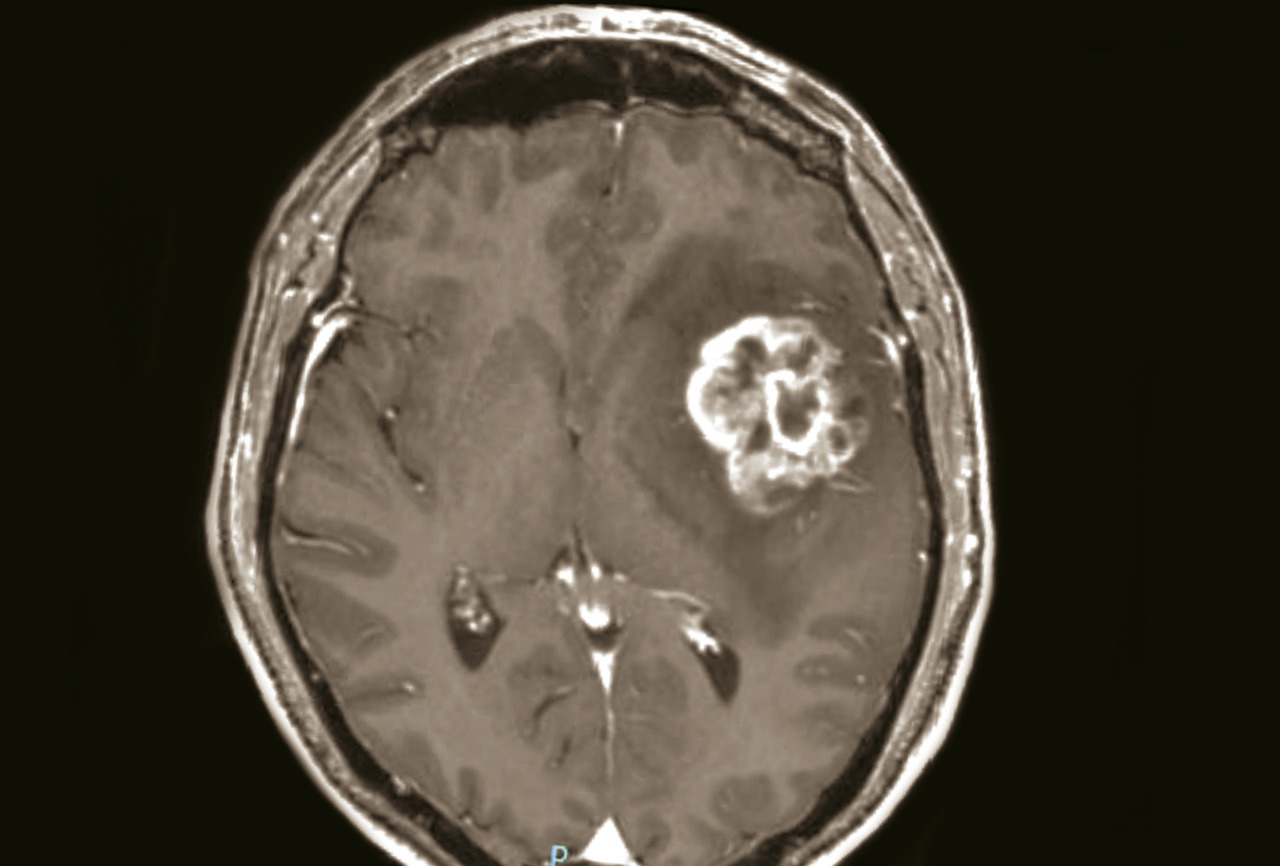

Une tumeur cérébrale peut se compliquer d’une hémorragie, favorisée par des facteurs intrinsèques à la tumeur (la néoangiogenèse tumorale dans les gliomes malins ; certaines métastases cérébrales sont plus volontiers hémorragiques, en particulier celles des mélanomes), ainsi que des facteurs systémiques (troubles de la coagulation induits par la tumeur, thrombopénie, anticoagulation à visée curative pour une phlébite ou une embolie pulmonaire, thérapies anti-angiogéniques). L’hémorragie intratumorale peut se manifester par une hypertension intracrânienne, un déficit focal d’installation aiguë ou la majoration d’un déficit déjà connu, une crise d’épilepsie. Elle peut être aussi asymptomatique et diagnostiquée à l’imagerie. Elle apparaît au scanner non injecté sous la forme d’une hyperdensité spontanée et à l’IRM non injectée par un hypersignal en T1 (fig. 8) et en hyposignal en T2* au sein de la tumeur.